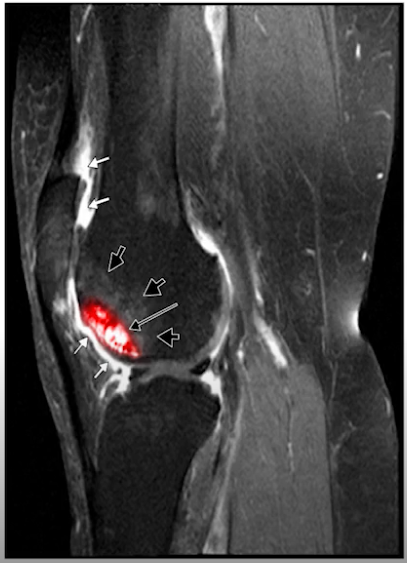

What is represented in this image?

Bone marrow lesions

What is the are the things indicated by the arrows and how does that influence OA?

That is infiltration of fragments of bone or cartilage into the synovium